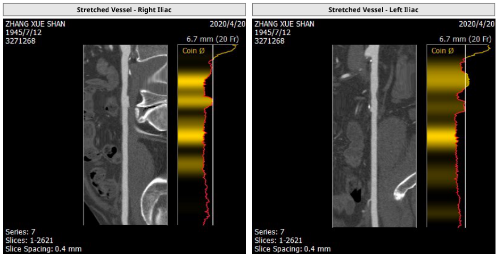

血管入路解剖: